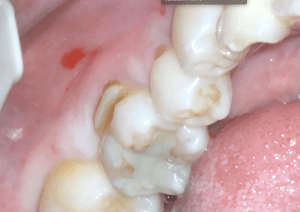

手前の不良充填物の再治療とWSD(くさび状欠損)

今回は手前の第二小臼歯、第一大臼歯の再治療も行うこととなりました。第一大臼歯は咬合面に古いコンポジットレジンによる修復が行われていますが接着不良による剥がれが起こっているようです。また、唇側歯頚部のエナメル質のくさび状欠損がおこっています。

CRの再治療を行う際には古い充填物を全て取り切ることが重要です。接着がうまくいっていないために起こったので確実に古い充填物を除去しています。